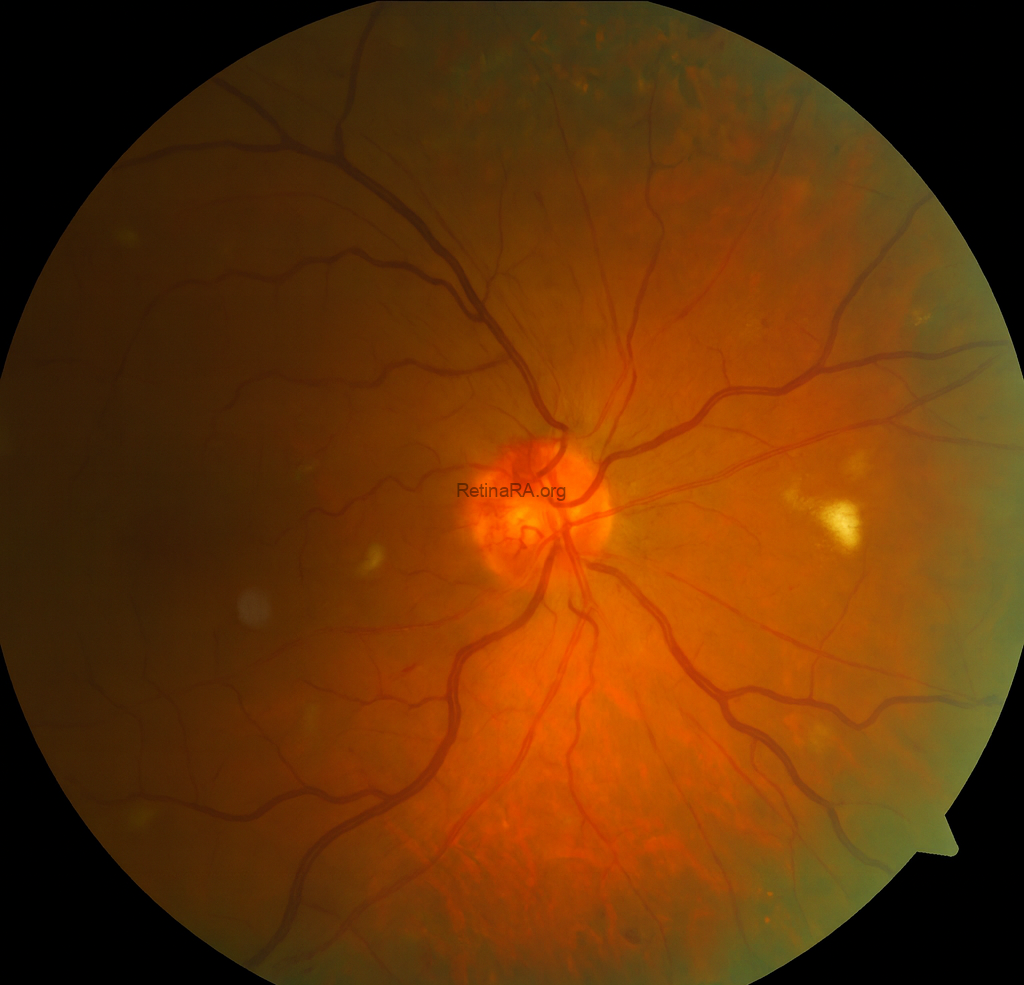

On ophthalmic examination, best-corrected visual acuity was 0.3 in the right eye and 1.0 in the left eye. Anterior segment findings were unremarkable in both eyes, and intraocular pressure was within normal limits. Fundus examination of the right eye revealed widespread intraretinal hemorrhages in all four quadrants, dilated and tortuous retinal veins, and cotton wool spots consistent with central retinal vein occlusion (CRVO). The left eye appeared normal.

The color fundus photograph demonstrates the classic features of central retinal vein occlusion. There are widespread intraretinal hemorrhages involving all four quadrants, producing the characteristic “blood and thunder” appearance. The retinal veins are markedly dilated and tortuous, reflecting venous congestion. The macular region is involved with hemorrhages and appears thickened, suggesting the presence of macular edema. Overall, the retina appears hazy because of diffuse edema, and the retinal arterioles are relatively attenuated compared with the engorged venous system.